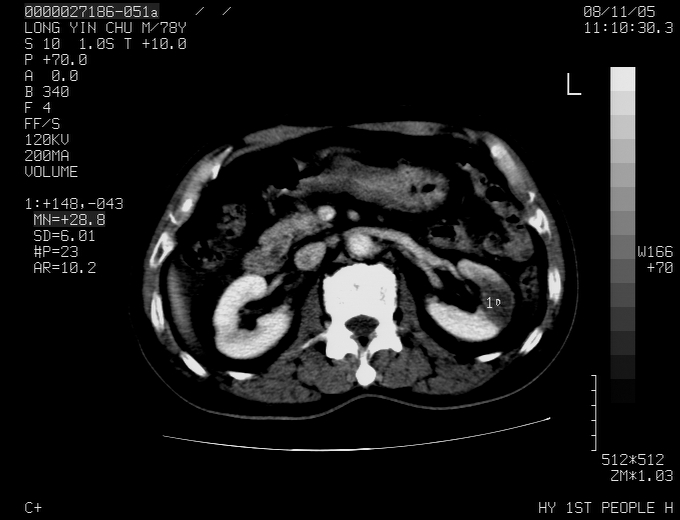

标题: CT16532:M78Y,肝脏病变,请会诊 [打印本页]

标题: CT16532:M78Y,肝脏病变,请会诊

腹胀,腹痛就诊,男性,78岁,外院b超未见异常。

肝ca,脾肾转移

考虑弥漫性肝癌并脾及双肾转移.双侧胸水.

图片质量欠佳:多考虑:左侧肾癌。脾脏转移!胸膜转移!

肝脾肾转移瘤可能性大,左肾不除外梗塞,双侧胸水

考虑弥漫性肝癌并脾及双肾转移,双侧胸水。